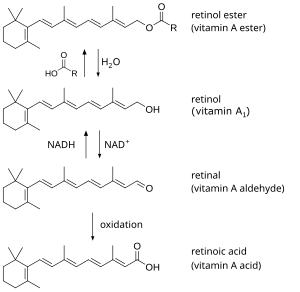

| Forms of preformed vitamin A in the body | |

Hypervitaminosis A refers to the toxic effects of ingesting too much preformed vitamin A (retinyl esters, retinol, and retinal). Symptoms arise as a result of altered bone metabolism and altered metabolism of other fat-soluble vitamins. Hypervitaminosis A is believed to have occurred in early humans, and the problem has persisted throughout human history. Toxicity results from ingesting too much preformed vitamin A from foods (such as fish liver or animal liver), supplements, or prescription medications and can be prevented by ingesting no more than the recommended daily amount.

Types of vitamin A

- It is "largely impossible" for provitamin carotenoids, such as beta-carotene, to cause toxicity, as their conversion to retinol is highly regulated.[19] No vitamin A toxicity has ever been reported from ingestion of excessive amounts.[22] Overconsumption of beta-carotene can only cause carotenosis, a harmless and reversible cosmetic condition in which the skin turns orange.

- Preformed vitamin A absorption and storage in the liver occur very efficiently until a pathologic condition develops.[19] When ingested, 70–90% of preformed vitamin A is absorbed and used.[19]